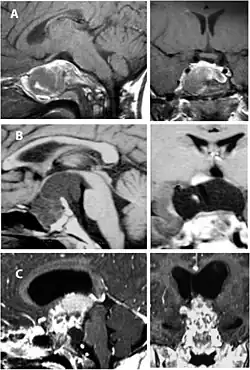

Imaging scans for craniopharyngioma

A physician can conduct a few scans and tests to diagnose a person with craniopharyngioma.[19] High-resolution magnetic resonance imaging (MRI) is commonly used as a diagnostic tool; however, computer tomography (CT) remains the gold standard imaging choice for craniopharyngioma diagnosis as it can detect the severity of the calcification within the tumour.[20]

In some cases, a powerful 3T (Tesla) MRI scanner can help define the location of critical brain structures affected by the tumor. The histologic pattern consists of nesting of squamous epithelium bordered by radially arranged cells. It is frequently accompanied by calcium deposition and may have a microscopic papillary architecture. A computed tomography (CT) scan is also a good diagnostic tool, as it detects calcification in the tumor.[21]

CT scan showing a craniopharyngioma -

Enhanced T1 weighted MRIs of craniopharyngiomas -